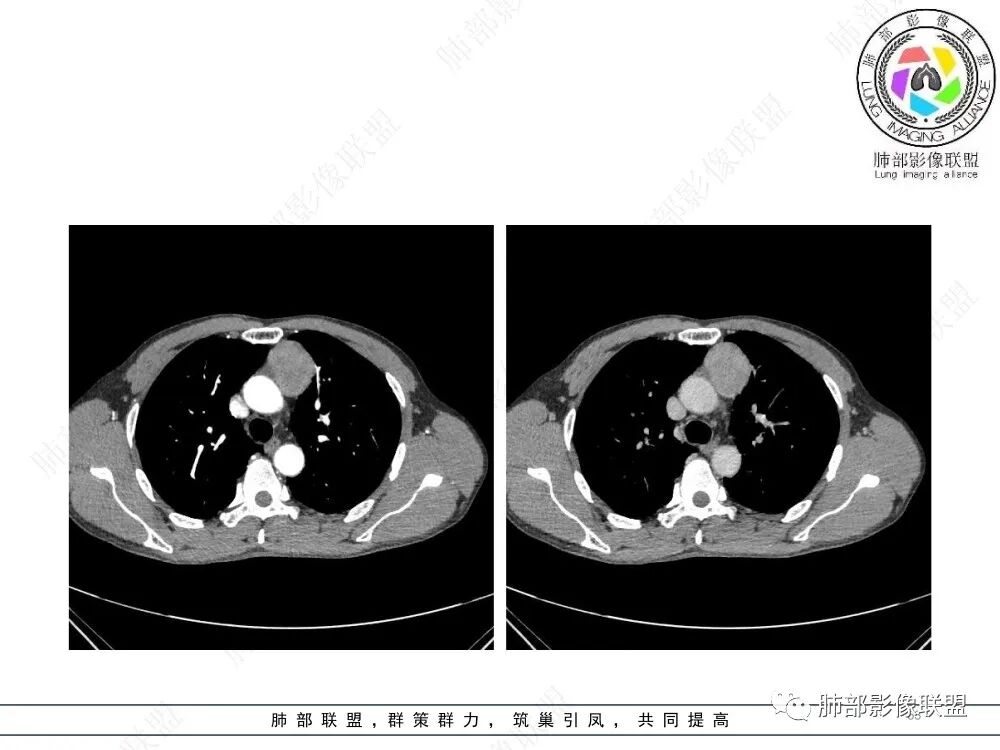

2、影像特点:前纵隔偏左侧软组织影,密度相对均匀,未见明显包膜钙化及实质内钙化,局部边缘浅分叶,周围脂肪间隙密度增高、浑浊,未见侵犯大血管、未见纵隔内淋巴结转移、未见侵犯心包内结构、未见胸膜转移结节、未见肿块沿着纵隔胸膜蔓延,未见胸腔积液。增强后动脉期不均匀强化,未见明显纤维分隔。

3、 病 例 小 结:40岁以上,前纵隔偏侧性生长的肿块,常规考虑胸腺瘤。难点就在于胸腺瘤的分型。但是对于前纵隔占位影像诊断的关键在于区分胸腺囊肿、胸腺瘤、胸腺癌及其他恶性肿瘤。至于胸腺瘤,主要在于判断有无侵袭性。

在路上:考虑胸腺瘤,密度均匀,无钙化,轻度强化,边缘请放射线:前纵膈偏左侧肿块,边缘光滑清晰,周围脂肪间隙清晰,渐进性强化,密度不均,考虑胸腺瘤,鉴别淋巴瘤。

lmg:前纵膈肿块,整体边界整齐,可见AB区,强化不均匀,可见延时强化,病灶内未见明显钙化,无分叶,考虑AB型胸腺瘤。